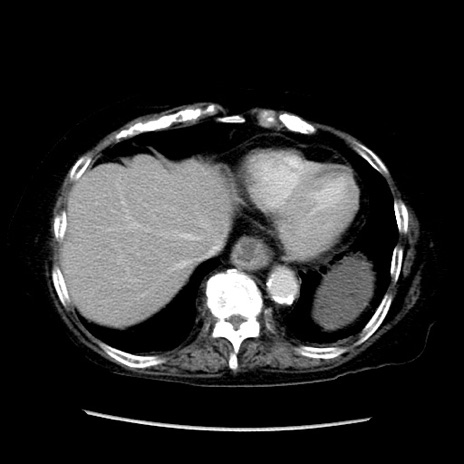

症例14(横断像)

【症例】 90歳代女性

【主訴】 腹痛・嘔吐

【現病歴】今朝から左側腹部痛を認めた。 経過観察していたが、嘔吐を認めたため来院。

【既往歴】 子宮癌術後

【身体所見】 意識清明、BP 127/54mmHg、P 98bpm Sp02 95%(RA)、BT 35.8°C、腹部平坦・軟腸ぜん動音聴取良好、右下腹部圧痛(+) 反跳痛なし

【データ】WBC 9800、CRP 0.46